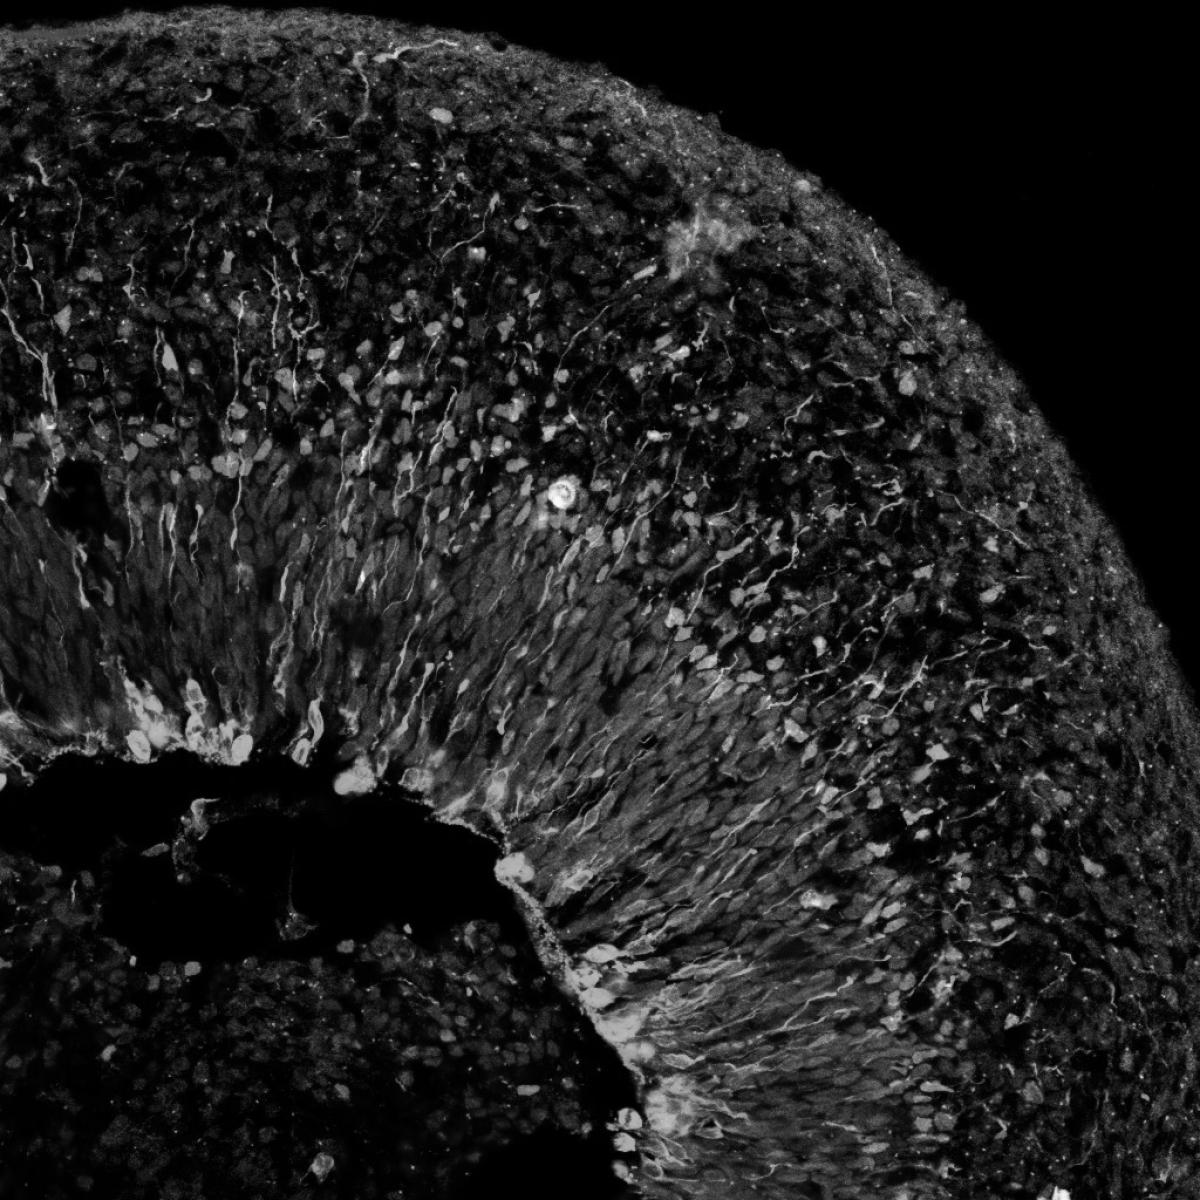

Atsushi (Austin) Nakano, M.D., Ph.D., studies how various types of diverse and specialized cells form the structure of the heart, deform during disease and reform after injury. He hopes this work will inform the development of novel regenerative treatments for heart disease and new approaches to reduce the risk of congenital heart defects.

Nakano’s experience as a cardiologist drives his research interest in the mechanisms underpinning embryonic heart development. He studies the regulation of the process through which stem cells arise from non-cardiac tissue during embryonic development, explores the molecular processes that inhibit the division of cardiac muscle cells and examines how the adaptability of cardiac cells to change and adopt characteristics of other cells contributes to cardiac development and disease.

While the postnatal mature heart has a limited capacity to regenerate, cells in the embryonic heart are plastic, or undifferentiated. Nakano has made two key discoveries that could have a profound impact on the development of cardiac stem cells that can be used to regenerate heart tissue following a heart attack: he found that immature cardiac muscle cells can change to become blood progenitor cells or the cells that make up blood vessels; and discovered that progenitor cells that normally give rise to blood stem cells can also give rise to cardiomyocytes.